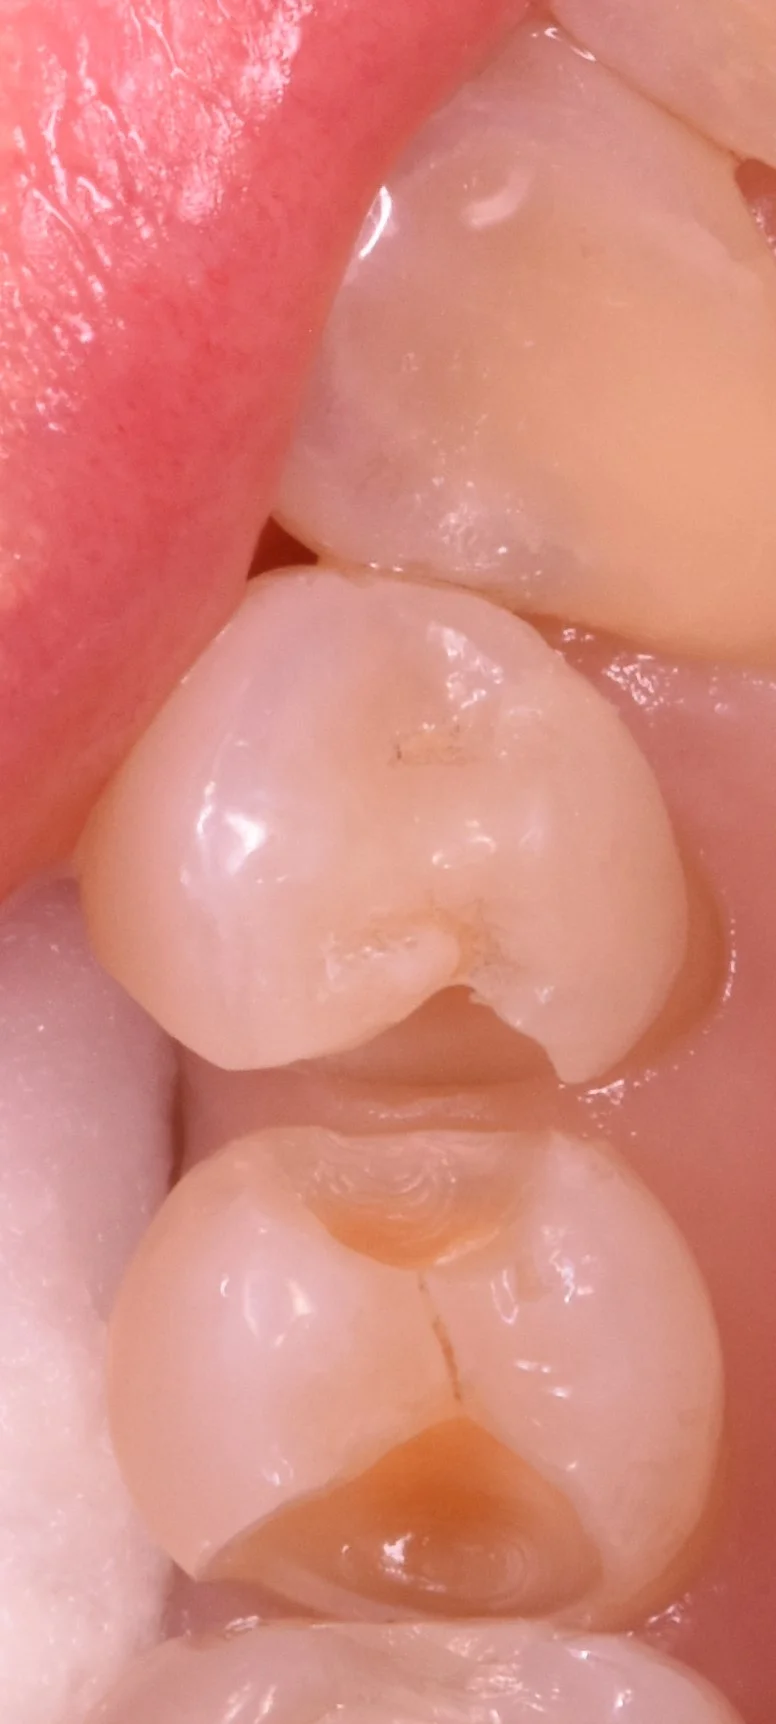

では術前の写真からです。

中央の2本の歯の治療になるのですが、後ろの歯が手前の歯に隠れているのが分かるかと思います。

これは歯の形もそうなのですが、虫歯によって出来た穴の部分に後ろの歯が食い込んでいってこうなっています。

削って軽く虫歯が見やすくなった状態がこちらです。

内面が茶色くなってしまっているのが分かるかと思います。

そして取りきったのがこちらです。

随分と綺麗に歯の色が出たかと思います。